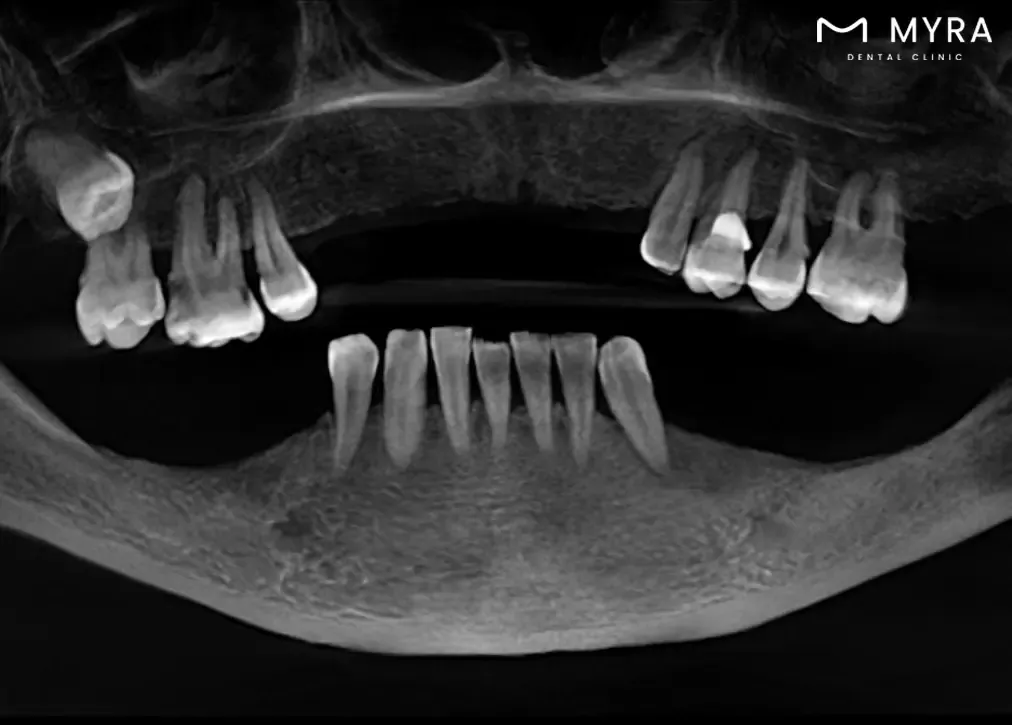

Sirona 3D Dental Tomography is a specialised imaging technique that falls under the category of dental computed tomography, offering a three-dimensional view of the oral and maxillofacial structures. 3D dental xray advanced technology allows for detailed and precise imaging, aiding dentists in comprehensive diagnostics and treatment planning.

The importance of Sirona 3D Dental Tomography lies in its ability to provide a more thorough understanding of dental and jaw-related issues. 3D xray is three-dimensional imaging capability allows dentists to visualise dental structures , bone density , and soft tissues with exceptional clarity , facilitating accurate diagnoses and effective treatment strategies . The innovative approach enhances the quality of dental care by offering a more comprehensive perspective, particularly in cases involving dental implants, surgeries, and complex dental procedures.

The working principle of Sirona 3D Dental Tomography involves capturing multiple X-ray images from various angles, which are reconstructed into a detailed three-dimensional image. The process ensures a more accurate representation of the patient's oral anatomy, allowing dentists to assess conditions with greater precision.

A 3D tomography X-ray shows a comprehensive view of the entire mouth, offering detailed insights into dental and jaw structures. The imaging method helps doctors better understand dental or jaw problems and come up with effective treatments by showing internal structures, bone density, soft tissues, and nerve distances. It makes it easier to diagnose dental problems such as cavities, buried teeth, fractures, bone defects, and other issues. It serves as a valuable tool in treatment planning, especially for dental implant placement, orthodontic procedures , and various oral health assessments , ultimately enhancing the success of treatments.

Dimensionality: Traditional dental X-rays are two-dimensional, presenting a flat representation of teeth and surrounding structures. Sirona 3D Dental Tomography offers three-dimensional imaging, allowing a more thorough analysis of dental and jaw anatomy from various angles.

Level of Detail: Traditional X-rays lack the depth and clarity necessary to visualise fine details and structures. Sirona 3D Dental Tomography provides high-resolution images, offering a more precise view of dental and jaw conditions, including bone structures and soft tissues.

Diagnostic Capability: Traditional X-rays are limited in their diagnostic capabilities for detecting certain conditions, such as subtle bone defects or complex anatomical relationships. Sirona 3D Dental Tomography enhances diagnostic accuracy, making it more effective in identifying a broader range of dental issues, from root canal configurations to bone density measurements.

Two-dimensional images are obtained in dental radiographs. In other words, with this type of imaging, you can learn about width and height, but you can't get clear information about the thickness of the tissue. Dental tomography is a three-dimensional image that provides more detailed and accurate information than X-rays. Especially hard tissues can be seen in more detail. In this way, the margin of error and error in the treatments to be done is less.